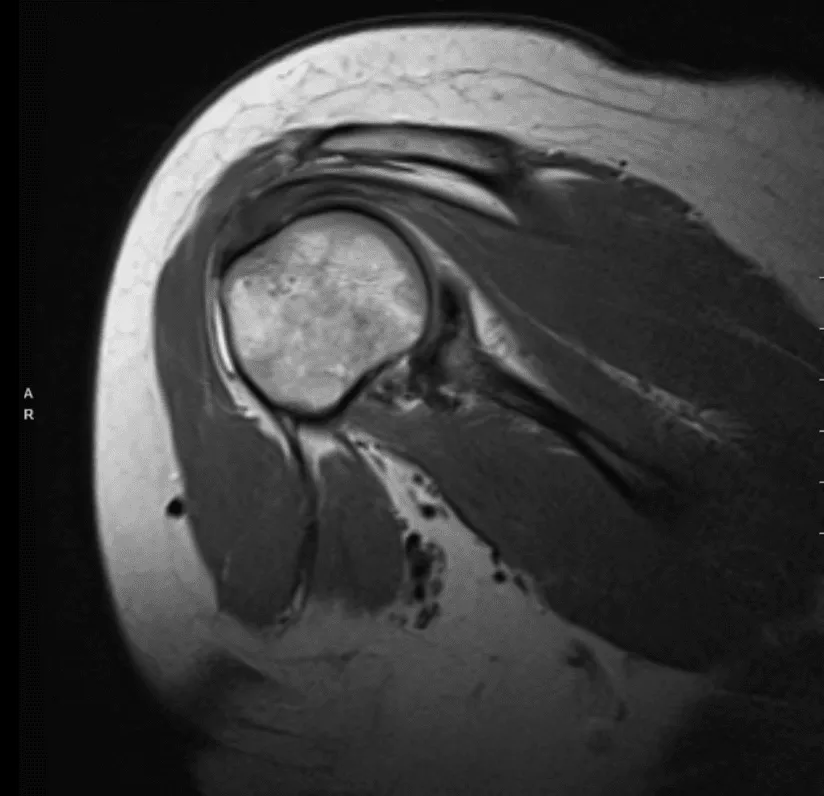

Realizó una resonancia magnética para el hombro derecho y mostró tendinosis difusa con una ruptura de grosor parcial de la huella de inserción anterior del tendón supraespinoso. Tendinosis difusa del infraespinoso con desgarro parcial intersticial. Tendinosis subescapularia.

Desgarro difuso del labrum superior/desgarro de SLAP. Desgarro del labrum posterior-inferior con desprendimiento parcial. Esguince capsular inferior frente a capsulitis adhesiva. Pequeño derrame. Quiste subcondral focal y defecto cartílago focal a lo largo del borde glenoideo posterior con patrón de desgaste subcondral temprano.

Bursitis subdeltoides subacromial. Cambio hipertrófico de la articulación AC con esguince capsular de grado I. Edema en la clavícula distal y el acrómio, que puede representar contusión o reacción al estrés. Estrechamiento del espacio subacromial. Edema de médula ósea con mayor tuberosidad compatible con la contusión ósea.

Resonancia magnética del hombro derecho